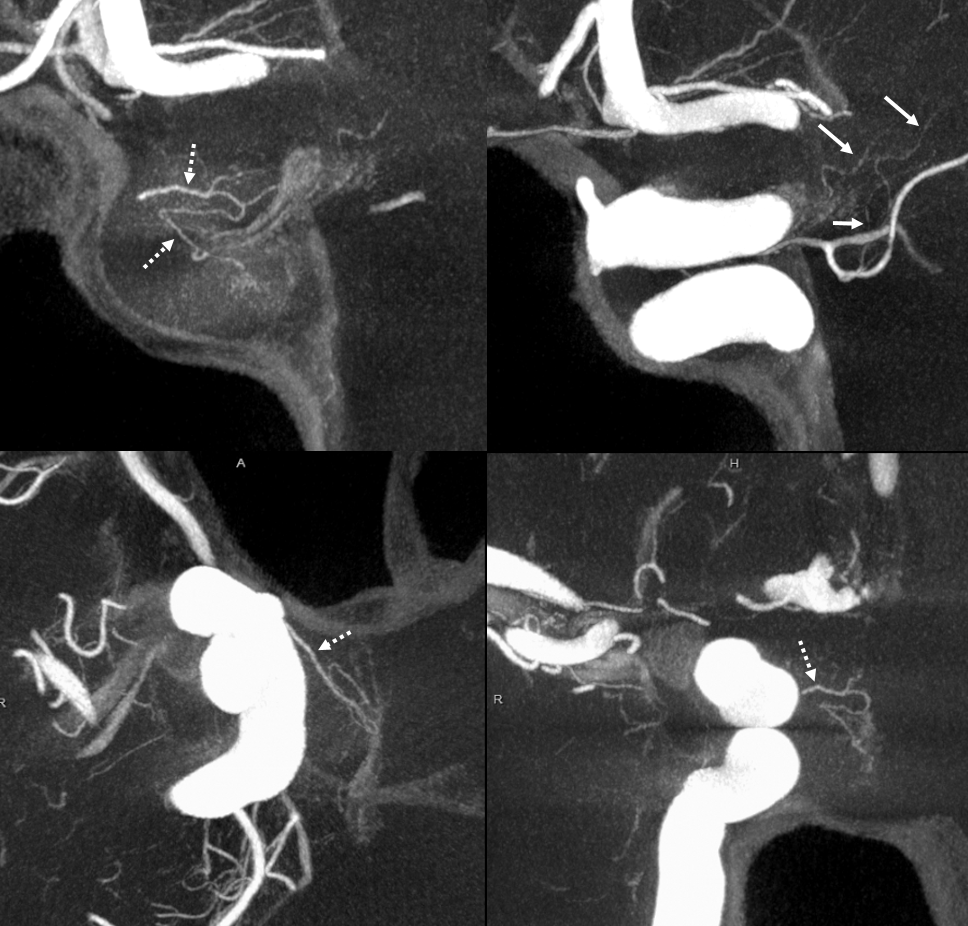

What supplies the bulk of optic nerve? Central Retinal artery is for the distal portion of nerve and retina. What about the rest — intracranial, intracanalicular, proximal intraconal segments? The answer is not clear (let me know if you do), but i believe the bulk of it comes from the superior hypophyseals. It is probably in balance with the recurrent branch of the central retinal artery. Below is an example of an especially prominent proximal-most superior hypophyseal (arrows) supplying the pituitary stalks and optic nerve in the canalicular and intracranial locations. Note how well one can see the branch in coronal view (bottom left image). In this case there are two large superior hypophyseals — the more distal one (dashed arrows) supplies predominantly the pituitary stalk. The inferior hypophyseal artery is marked by arrowhead. Lower right image is coronal.

Movie is the best way

Here too superior hypophyseal (arrow) supply of the intracranial optic nerve (oval) and possibly chiasm is shown definitively (lower right image is coronal)

No annotations

Best seen in this movie (pause to scroll)

Pattern of optic apparatus supply and unusual hypophyseal ILT vessel

VR — the anterior-most branch of the superior hypophyseals is usually the largest (arrow). The others are too small to see on a VR image

MIPS. The anterior, proximal-most branch (arrow) tends to supply the optic nerve (white oval), while the more posterior branches (dashed arrows), when present, supply more posterior structures such as chiasm and tract (dashed oval)

A highly unusual branch originating from ILT region swings underneath the cavernous ICA and supplies the floor of the pituitary fossa. Yet unknown, as far as i know

More Optic Nerve Supply — its easier to see on MIPS, but with the right windowing, and stereo, VR imaging is also possible. Here, there are 3 superior hypophyseals seen. The anterior-most (arrow) is usually the largest, suppling the optic nerve (dashed arrow) and chiasm (ball arrow). The middle and posterior hypophyseals (arrowheads) supply the stalk.

Stereo of VR image. Same arrows. The stalk is open arrow.

Another patient — also 3 arteries. Cave origin of the anterior-most (arrows) one. The middle one (arrowheads) also supplies the optic nerve. The posterior one (dashed arrows) is for the stalk.

VR images (stereo pair on bottom). The cave origin of the anterior branch is most beautifully seen in the upper right image.